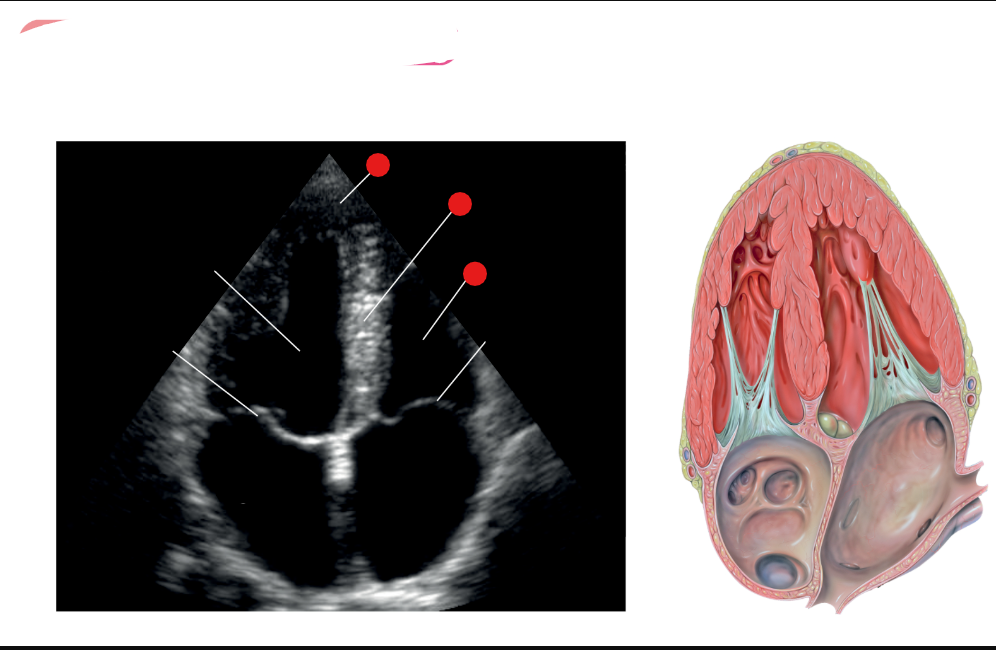

what are the white labels

RV

LA

LV

LVOT

AO

What is this view

parasternal long axis of the heart

What view is this

label red